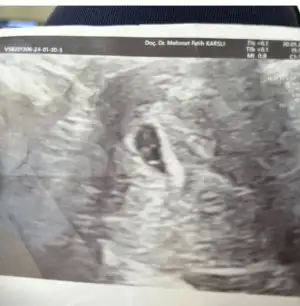

T Tali89 üstad sen bu işi nasıl yapıyorsun bi anlatCihazı bastırınca kese şekli değişiyor ama boyle goruntulerde var 5-6 hafta bi tanesinde yolk sac gorunmuyor ama fotografa basmamıs goruneni

Eki Görüntüle 3384379